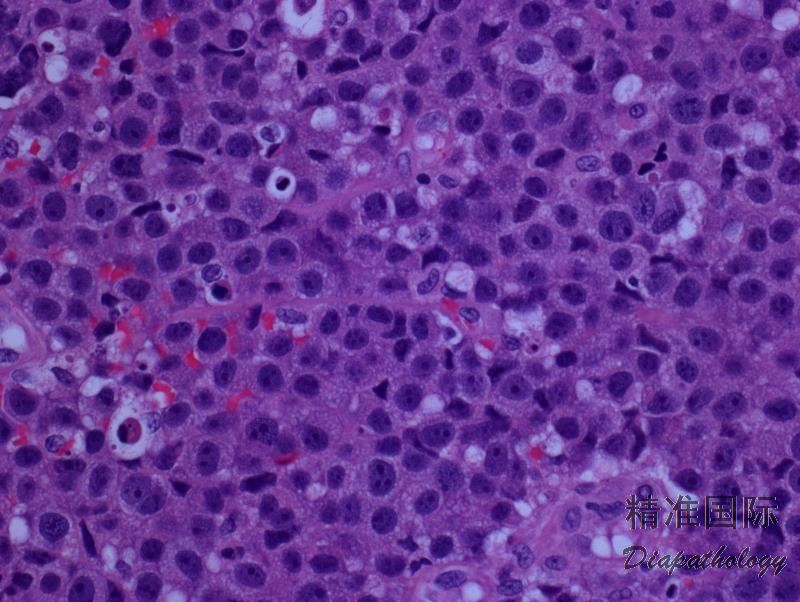

多数病例肿瘤细胞呈现间变性形态(园或椭圆形核、核不规则、显著嗜伊红核仁、丰富胞质),但也可呈现多形性或免疫母样细胞形态。

肿瘤细胞弥漫浸润,主要累及真皮层,可延及皮下组织,但有时见亲表皮浸润,特别是有 DUSP22-IRF4 病例。病灶周围可见少量背景炎性细胞,但如有溃疡,则常伴有丰富炎性细胞常(类似 LyP)。罕见病例含大量中性粒细胞(中性粒细胞富有亚型)。